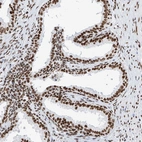

Immunohistochemical staining of human prostate shows strong nuclear positivity in glandular cells.